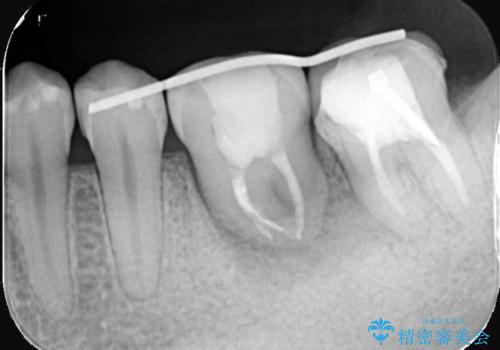

保存が難しい左下6番目の歯を抜歯し、左下8番目の歯(親知らず)を抜歯窩に移植しました。歯牙移植後の動揺防止のため暫間固定を行っています。

また移植後2週間経過時点で根管処置が必要となります。